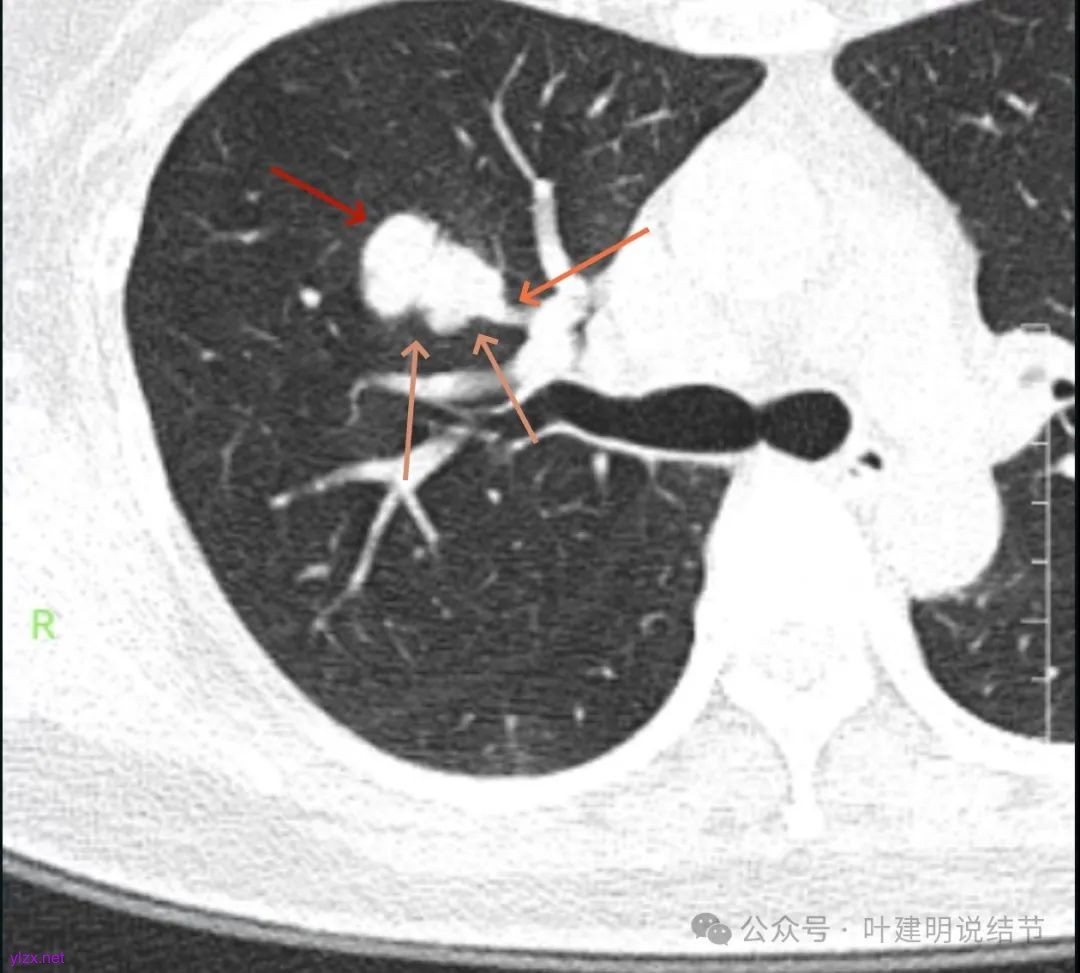

影像展示与分析:

腔静脉旁明显肿大淋巴结。

你的右上叶这个病灶基本上肯定是肺癌,要尽快处理。从影像上看有以下特点:1、整体轮廓清楚,不似普通炎症的周围有晕或阻塞性改变;2、边缘明显的浅分叶,总体上的感觉膨胀性明显,不管哪个层面看上去都是鼓鼓的;3、边缘区域有磨玻璃成分而且也是分叶状的;4、部分层面见血管进入;5、空腔病灶的壁厚薄不均,内壁不光滑。我考虑中低分化肺癌,由于腔静脉旁有明显肿大淋巴结,需要进一步完善增强CT以及PET-CT检查以明确有无远处转移,是否仍可手术治疗(从病灶本身来说是可以肺叶切除治疗的)。要尽快处理。意见供参考!